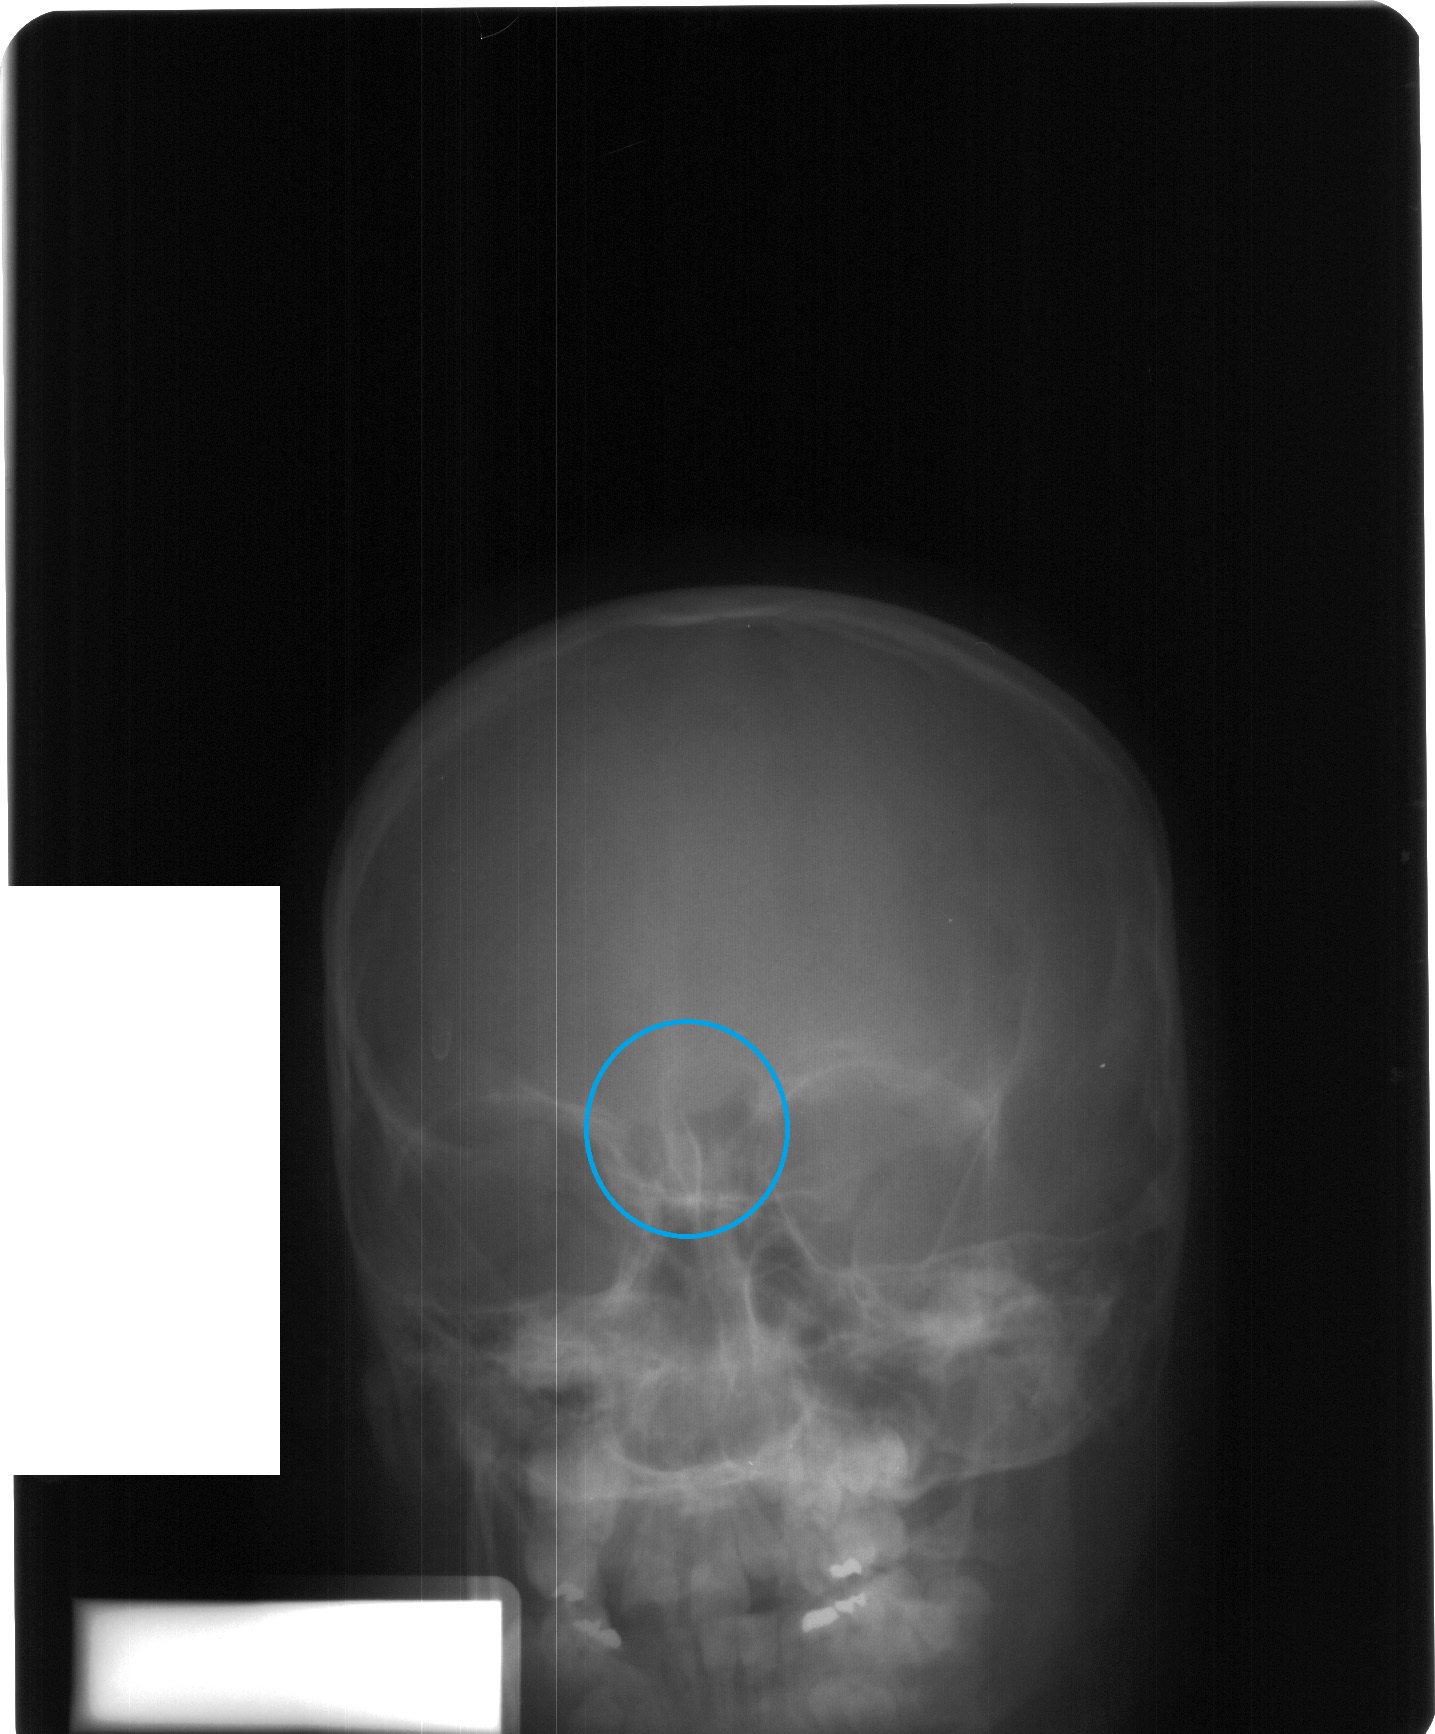

Juvenile skull showing stage two of frontal sinus development.

Frontal sinuses grow and begin to bump up against each other around ages 7 to 10. North Carolina State University

The study described four phases of frontal sinus development of the skull using X-ray images of 392 juveniles: complete lack of frontal sinus development (ages six and under), development of two small, kidney-bean-shaped areas around the front of the forehead (six to eight), initial stages with two cavities that touch but don’t merge (seven to ten), and fully-formed merging frontal sinuses (twelve to eighteen).